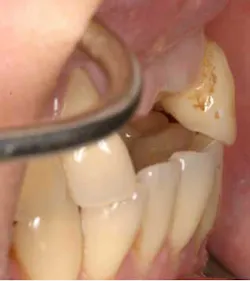

A 43-year-old female with a noncontributory medical history taking no medication and having no known food/drug allergies presented to my general dental office with a chief complaint of having “loose teeth with an underbite.” Clinically, she had generalized, moderate, chronic periodontal disease and was missing teeth Nos. 8 through 10. She had a Class III malocclusion with pathologic flaring of her remaining anterior teeth. She had both vertical and horizontal tissue loss in the No. 8 through 10 region. The patient wore a transitional partial denture to replace the anterior missing teeth that was placed in edge-to-edge occlusion by her previous dentist. (Fig. 1) She did not like having a removable prosthetic and desired a fixed option in the form of implants to replace her missing teeth. I sent her to the periodontist for a periodontal consult for her remaining dentition and dental implants to replace her missing front teeth.

Fig. 2